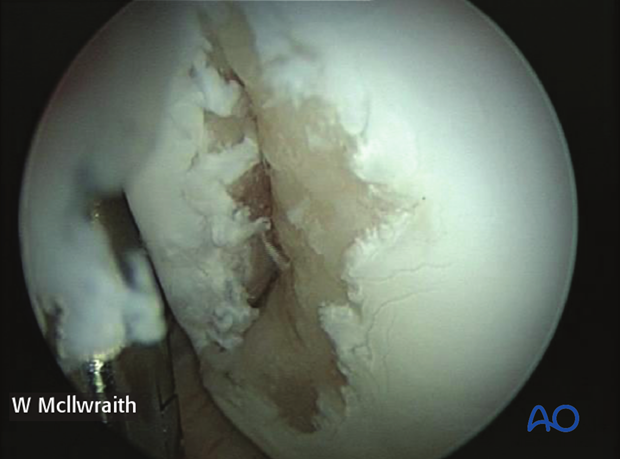

The dorsal compartment of the middle carpal joint should then be evaluated completely and any additional lesions noted. Non-displaced fractures have variable amount of cartilage disruption.

Any loose cartilage and bone debris is debrided.

This picture shows the defect after removal of an osteochondral wedge at the proximal limit of fracture.